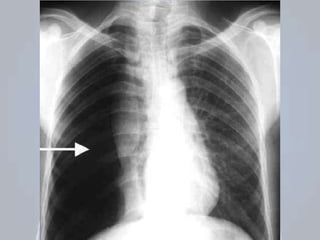

HEMOTÓRAX

 Presença de sangue no espaço pleural;

 Representa fonte de perda sanguínea importante;

 Mesmos mecanismos do pneumotórax;

Origem: parede da musculatura torácica, vasos

intercostais, parênquima pulmonar, vasos

pulmonares ou grandes vasos do tórax;

AVALIAÇÃO: desconforto; dor torácica e a dispneia;

Sinais de choque: taquicardia, taquipneia, confusão,

palidez e hipotensão.

EXAME FÍSICO: sons respiratórios são diminuídos

ou ausentes; percussão é abafada;

PNEUMOTÓRAX + HEMOTÓRAX: probabilidade de

comprometimento cardiorrespiratório;